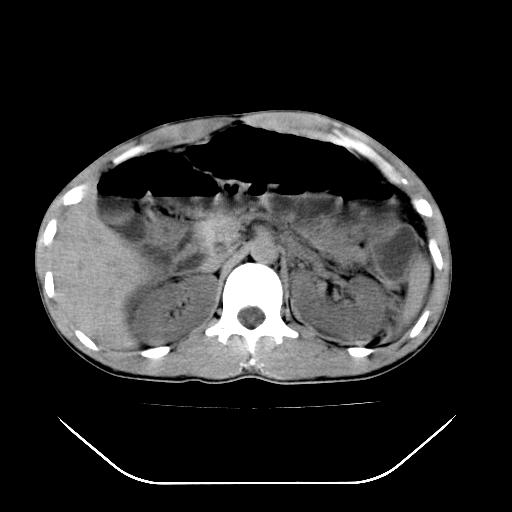

m-25y 高空堕落 12 月5号

12月7号病人尿量200ml/24h 急查双肾ct

左肾挫裂伤并肾周血肿;

12月7号

肝肾间隙可见液区,建议手术探查;

左肾挫裂伤并肾周血肿

支持 : 左肾挫裂伤并肾周血肿

支持:1、左肾挫裂伤并肾周血肿;

2、少量腹水;

3、左肾旋转不良;

4、反射性肠淤张。

除了1:左肾挫裂伤并肾周血肿;

2:少量腹水

第二次ct检查后:临床医生腹水穿刺后考虑肠系膜动脉破裂,后实行剖腹探查:于空肠距离十二指肠90cm处发现肠管破裂,破裂口较小;修补后关腹。